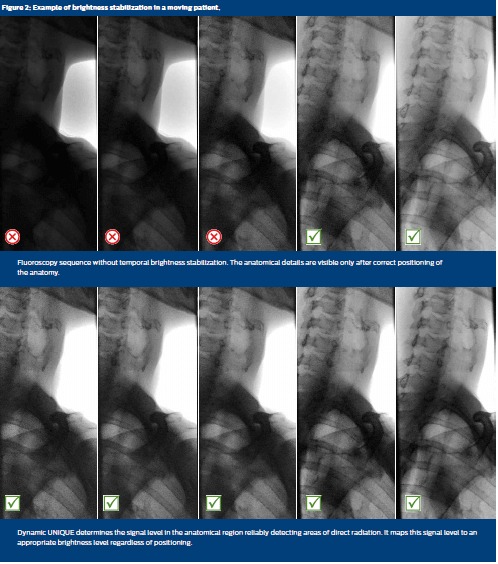

When the dose level or the field-of-view is modified (e.g. by modifying its size, by shifting it from the body center to the periphery, or by moving the patient), Dynamic UNIQUE automatically determines the signal level in the anatomical region and maps it to an appropriate brightness level. Areas of direct radiation are reliably detected and excluded from the brightness adjustment. In contrast, simpler methods include areas of direct radiation in adjustments, resulting in dark images and obscured anatomy, as well as annoying flickering.